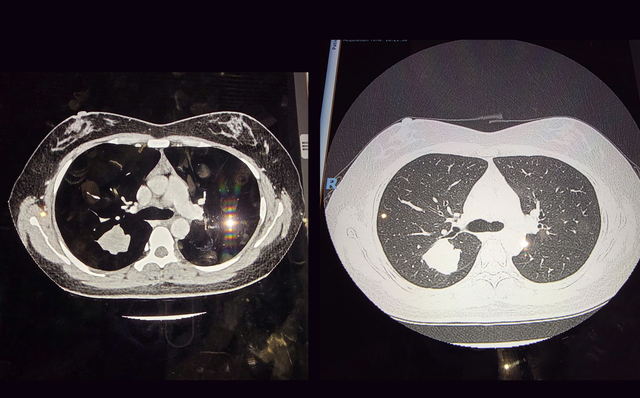

Đi khám kiểm tra sức khỏe tổng quát định kỳ là thói quen mà chị C. đã duy trì suốt nhiều năm. Chưa một lần nào kiểm tra sức khỏe khiến chị phải lo lắng. Mang tâm lý đầy tự tin trong lần khám định kỳ năm nay, nhưng kết quả chụp CT ngực liều thấp đã khiến chị và gia đình như chết lặng khi bác sĩ cho biết đã phát hiện một khối u bên trong phổi.

Nhờ người quen giới thiệu, gia đình đưa chị C. đến Bệnh viện Nam Sài Gòn để kiểm tra chuyên sâu, dưới sự theo dõi trực tiếp của Phó giáo sư - tiến sĩ - bác sĩ Vũ Hữu Vĩnh, chuyên gia hàng đầu về phẫu thuật lồng ngực, đang công tác tại bệnh viện.

"Khi nhận được kết quả, tôi không khỏi ngạc nhiên vì chị C. có tổn thương tân sinh phổi phải (khối u ở phổi phải). Điều khiến tôi bất ngờ hơn cả là một người khỏe mạnh, còn khá trẻ như chị C. lại có nguy cơ mắc u phổi", bác sĩ Vĩnh bày tỏ.

Ngay lập tức, ca phẫu thuật nội soi lồng ngực được chỉ định. Ê kíp phẫu thuật gồm Phó giáo sư - tiến sĩ - bác sĩ Vũ Hữu Vĩnh, bác sĩ chuyên khoa 1 Phạm Phú Khang (cựu bác sĩ nội trú), phối hợp cùng đội ngũ gây mê hồi sức, đã tiến hành thăm dò và phát hiện khối u tại phân thùy S2 có kích thước khoảng 4×3 cm, rắn chắc và co kéo nhu mô phổi.